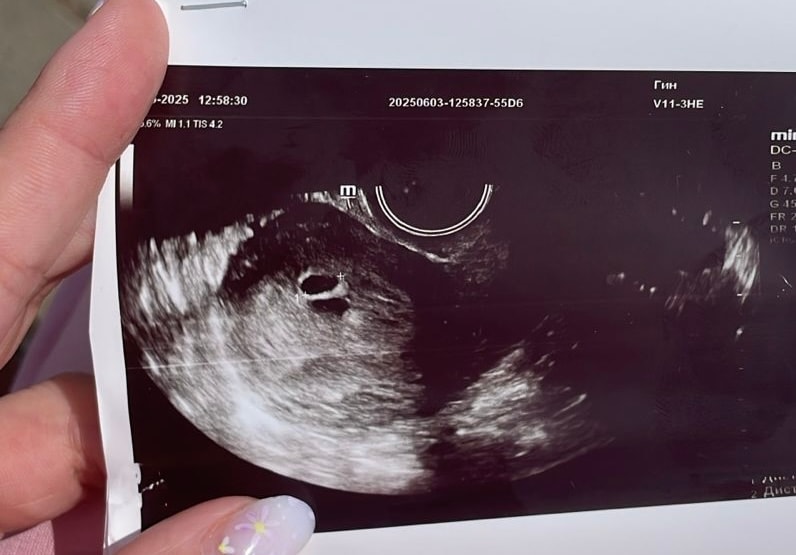

Ксеня, так вот на узи же хорошо видна гематома … странно ! Темный овал под плодным яйцом

Ксения , на двух узи была вчера. На втором узи заподозрили 2е пя. Но так как срок 4-5 недель,еще не понятно.это узи из друго клиники,вчера напугалась,решила сходить перепроверить

Ксеня, тут уже реально похоже на 2 ПЯ, только контур почему тогда не сомкнут.. Может просто маленький срок и просто плохо видно , удачи вам!

Ксения , тако аппарат( к сожалению,попала на сохранение сегодня 🥺

Делали снова узи,точно 2